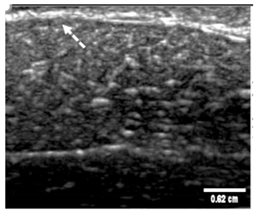

3.3. B-Mode Images

3.5. Echogenicity

4.1. Ultrasonography and Aerogel Dimensional Analyis

| Aerogel Type | US Image | Normalized Intensity Map | 3D Intensity Map | |

|---|---|---|---|---|

| 1 | Muscle |  |  |  |

| 2 | X-silica |  |  |  |

| 3 | X-silica-La2O2S:Eu |  |  |  |

| 4 | SMPU-Mix-14 |  |  |  |

| 5 | SMPU-Mix-18 |  |  |  |

| 6 | BRF-CA |  |  |  |

| 7 | ARF-CA |  |  |  |

| 8 | X-Ca-Alg-2 |  |  |  |

| 9 | X-Ca-Alg-1 |  |  |  |

| Aerogel Type | Imaging Frequency (MHz) | Optimal Frequency (MHz) | Echogenicity | Image Characteristics | Impedance Mismatch (%) | |

|---|---|---|---|---|---|---|

| Subcutaneous | Submuscular | |||||

| X-silica | 6.5–13.4 | 13.4 MHz | Hypoechoic | Least Hyperechoic | Distinct linear boundary | 92.03 |

| X-silica-La2O2S:Eu | 6.5–13.4 | 13.4 MHz | Hypoechoic | Least Hyperechoic | Distinct linear boundary | 90.28 |

| SMPU-Mix-14 | 6.5–13.4 | 11 MHz | Hyperechoic | Moderately Hyperechoic | Irregular boundary | 98.33 |

| SMPU-Mix-18 | 6.5–13.4 | 11 MHz | Hyperechoic | Moderately Hyperechoic | Irregular boundary | 98.23 |

| BRF-CA | 6.5–13.4 | 13.4 MHz | Hyperechoic | Hyperechoic | Waterfall appearance | 97.16 |

| ARF-CA | 6.5–13.4 | 13.4 MHz | Hyperechoic | Hyperechoic | Waterfall appearance | 97.12 |

| X-Ca-Alg-2 | 6.5–13.4 | 11 MHz | Isoechoic | Strongly Hyperechoic | Irregular boundary | 98.03 |

| X-Ca-Alg-1 | 6.5–13.4 | 11 MHz | Isoechoic | Strongly Hyperechoic | Irregular boundary | 97.97 |